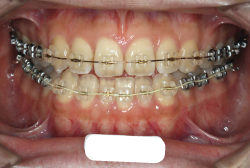

「前歯が重ならない」という主訴で来院したケースです。診断の結果、「重症の開咬」と判明しました。

この方の場合は、マルチブラケット装置は、歯の位置づけを3次元的に正確に行うことの出来る最善の矯正方法です。したがって開咬の治療も、形の改善としては問題なく行うことが出来ます。しかし、開咬が他の症状と少し違う点は、舌や唇の動かし方に問題があることから生じた症状なので、この問題を放置したまま形だけを作っても、時間が経つと簡単に後戻りしてしまうという問題です。つまり、マルチブラケット法で形態の矯正をするのと同時に、原因となっている筋肉の動きを正常に修正しなければなりません。この筋肉の動きを正常に修正する治療が、"筋機能訓練療法(Myo-functional therapy:略してMFT)"といわれるものです。

筋機能訓練療法は、筋機能訓練療法士という特別なトレーニングを積んだ歯科衛生士が行います。内容的には、いろいろなメニューがあり、簡単なものから始めて少しずつ筋肉の力を強めていき最終的には、無意識に起きる舌の突出をなくし、正しい摂食嚥下運動を獲得するまでトレーニングしていきます。この症例は、もちろん筋機能訓練にもしっかり取り組みました。治療後は開咬が改善しただけでなく、出っ歯の症状もなくなり唇の審美性が大幅に改善しました。もちろん奥歯の噛み合わせも正しい状態が確立しています。